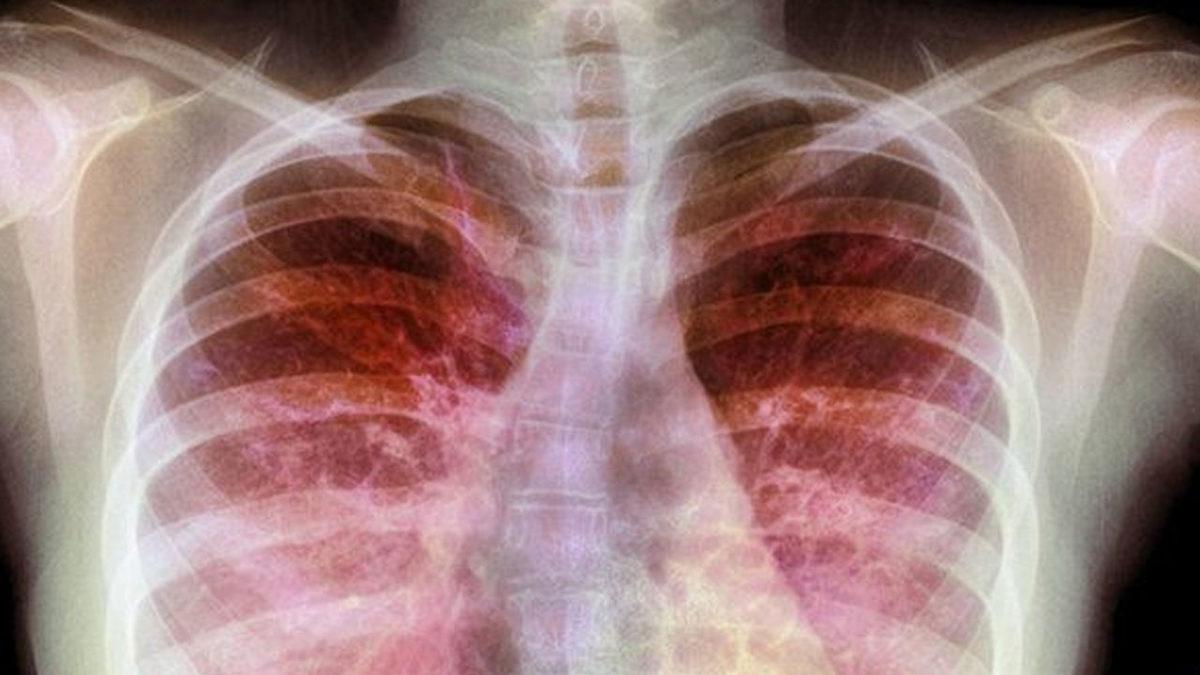

Bilim dünyası için aslında yeni bir şey olmayan koronavirüs, daha önce 2 kez daha insanlığı vurmuştu. Ancak 2020’de yaşanan son salgına neden olan yeni tip koronavirüse karşı, daha önceki koronavirüs salgınlarında kullanılan ilaçlar şimdilik yanıt vermedi. Yeni tip virüsün neden olduğu ağır solunum yolu enfeksiyonlarına karşı ise bilimsel çalışmalarla daha önce elde edilen sonuçlar önem kazandı. Prof. Dr. Ercüment Ovalı ve ekibi ise çalışmalarını daha Dornaz Alfa üzerine yoğunlaştırdı.

Dornaz Alfa ya da İngilizce literatürdeki adıyla Dornase Alpha, aslında yaygın görülmeyen bir solunum hastalığı olan “kistik fibroz” vakalarında bulunan bir tür etken maddedir. Dornaz Alfa etken maddesi, bu hastaların balgamlarında bulunan DNA’yı hidrolize ederek katılaşan mukozayı akışkan hale getirir.

Dornaz Alfa isimli bu etken madde, solunum yollarını rahatlattığı keşfedildikten sonra, Pulmozyme gibi isimlerle ilaç şeklinde alınabilmesi için yapay olarak da üretilmiştir. Bu sayede sadece kistik fibroz hastaları değil, benzer sorunlar yaşayan diğer hastalarda da kullanılmıştır. Yapılan son dönem çalışmalarıyla Dornaz Alfa’nın koronavirüsün neden oluğu Covid-19 hastalığına karşı da etkili olduğu tespit edilmiştir. Ancak çalışmalar henüz tartışılma aşamasındadır, ilk sonuçlar yanıltabilir, kesinlik yoktur.